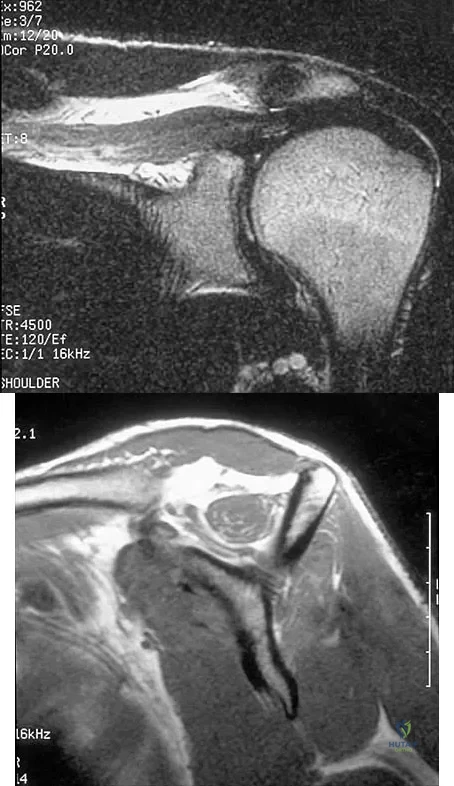

Figures 36a and 36b show the MRI scans of a patient who has shoulder weakness. What is the most likely diagnosis?

Explanation